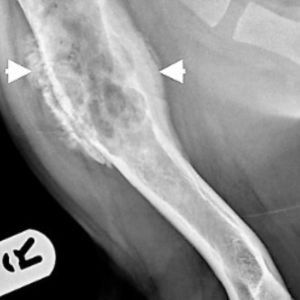

4. Osteosarcoma (cáncer de hueso)

- Es muy agresivo y frecuente en razas grandes como el Gran Danés o el Rottweiler.

- Afecta principalmente las extremidades, causando cojera y dolor.

- El diagnóstico suele ser tardío, y el tratamiento incluye amputación y quimioterapia.

- Tiene alta tasa de metástasis pulmonar.

- Radiografías: útiles para detectar tumores óseos, masas torácicas o abdominales.